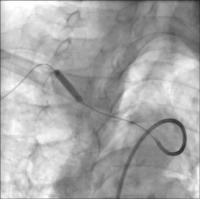

Postdilatation

Abbildung 5: Postdilatation (Pheron™, Biotronik, 8x20 mm/135 cm)

Abschlußangiographie

Abbildung 6: Abschlußangiographie mit guter Stentplazierung bei uneingeschränkten Flußverhältnissen in der Arteria carotis communis und antegradem Fluß in der Arteria vertebralis.